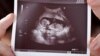

თუ შარშან, კოვიდინფექციით ერთი ორსული გარდაიცვალა, 2021 წელს 8 ასეთი შემთხვევა დადასტურდა. იმატა კორონავირუსით ბავშვთა ინფიცირების რიცხვმაც.

მიუხედავად იმისა, რომ პანდემიის გავრცელებისას ცნობილი იყო, რომ კორონავირუსი ორსულებსა და ბავშვებს არ „ერჩის“, დელტა შტამმა რეალობა შეცვალა. ინფიცირდებიან ორსულებიც, როგორც ამ პერიოდში სუსტი იმუნიტეტის მქონე ადამიანები და ბავშვებიც, რომელთა რიცხვი მუდმივად იზრდება.

ვაქცინაცია, მშობლების გარდა, დედის მუცელში მყოფ ბავშვებს და მეძუძურ ჩვილებსაც რომ შეიძლება დაეხმაროს, ეს კარგად იცის სოფო გვანცელაძემ, რომელიც მალე დედა გახდება. ამბობს, რომ ბევრი რამე წაიკითხა იქამდე, სანამ აცრას გადაწყვეტდა.